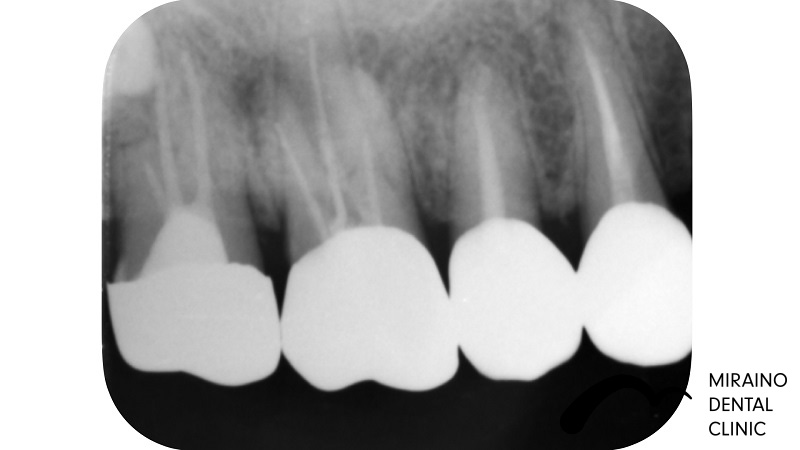

無菌的根管治療→被せ物・メタルフリークラウンの症例

Case1

| 施術名 | 無菌的根管治療 |

| 治療の概要 | 噛んだ時の違和感・歯ぐきにできものができるということで来院されました。 過去に神経の治療を行なっている場所の再発でした。 治療中の唾液による感染を防止するため、 ラバーダムを用いて無菌的に歯の根の中・根の先の感染の除去治療を行いました。 6ヶ月経過観察後、感染再発の症状が見られなかったため、 汚れのつきにくい素材で被せ物を装着しました。 |

クリックして詳細を表示

| 施術の内容 | 歯の根の中・根の先の感染の除去します。 ラバーダムを用いて唾液による感染のリスクを排除し無菌的な治療を行います。 感染・炎症の所見が無くなれば抗菌作用のある材料で根っこの通り道を封鎖します。 ラバーダム を用いて唾液による感染のリスクを排除し無菌的な治療を行います。 |

| 1歯あたりの治療費 | 1根:15,000円 |